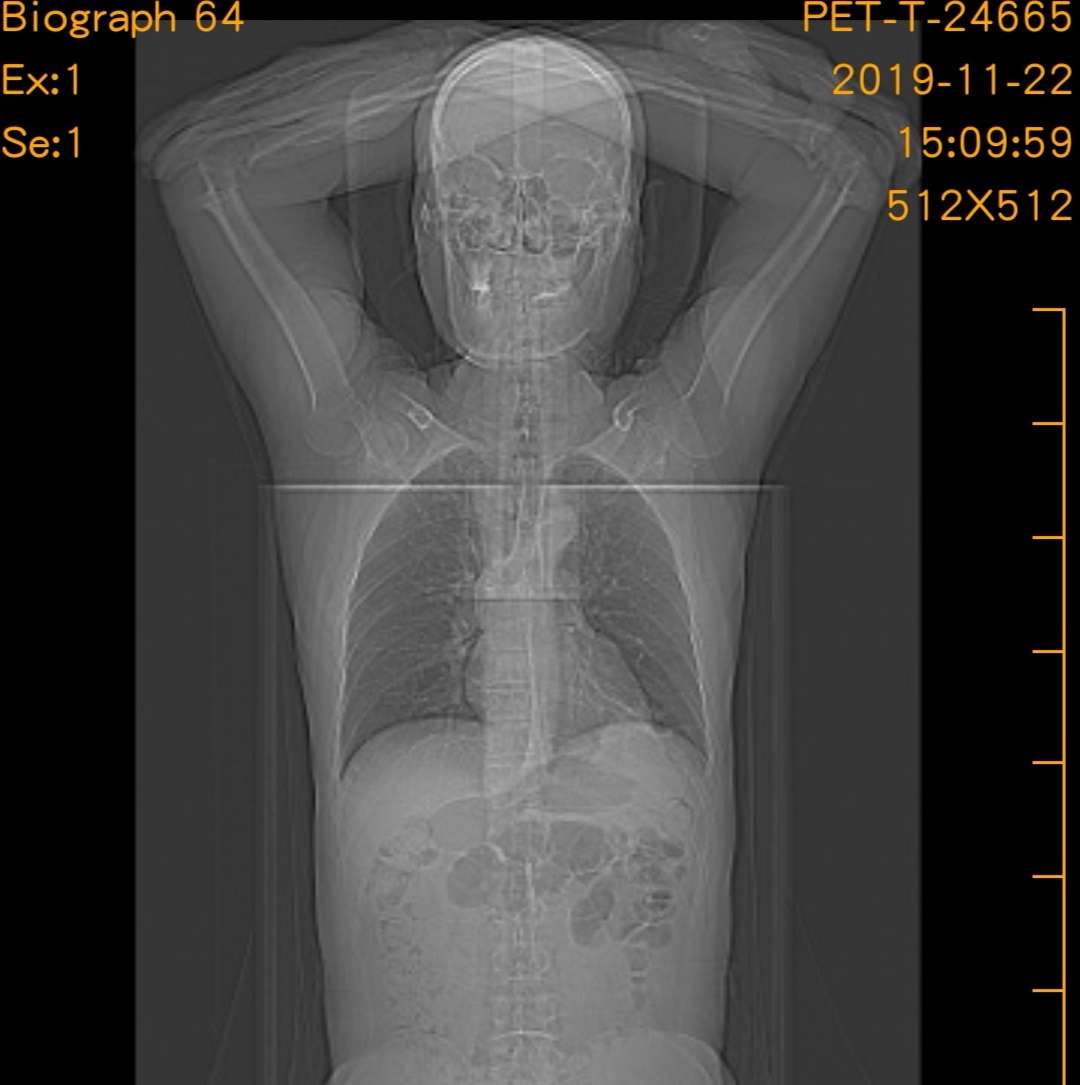

这是确诊时的pet ct